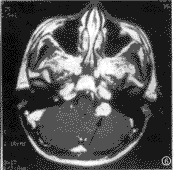

图1 右侧颈静脉球瘤,横轴位T1WI示右侧颈静脉孔区病灶呈等信号(黑箭),其内可见明显流空(箭头)

图2 与图1同一病例增强后,病灶明显强化(白箭)

本组颈静脉球瘤发生在右侧5例,左侧2例。其中1例于颈静脉孔区和中耳鼓室各见一病灶,3例病灶局限于颈静脉孔区,2例病灶主要位于颈静脉孔区,同时侵犯中耳,1例病灶亦主要位于颈静脉孔区,但同时侵犯内耳道口。7例病变中有2例尚侵入乙状窦沟,2例压迫小脑前缘,1例包绕舌下神经,2例紧贴舌下神经。CT显示6例颈静脉孔区均有明显骨质破坏,1例仅见颈静脉增粗并伴颈静脉窝高位。术前定位诊断皆正确,4例定性诊断正确,1例诊断为颈静脉孔区恶性肿瘤,1例诊断为炎性病变,1例诊断为颈静脉窝高位。MRI显示病灶形态皆不规则,T1WI上均呈近肌肉之等信号,T2WI上3例信号与肌肉相近,4例信号较肌肉稍高。所有病灶内均可见不同程度的流空表现,增强后所有病灶均有明显强化(图1~4)。MRI定位与定性诊断全部正确。